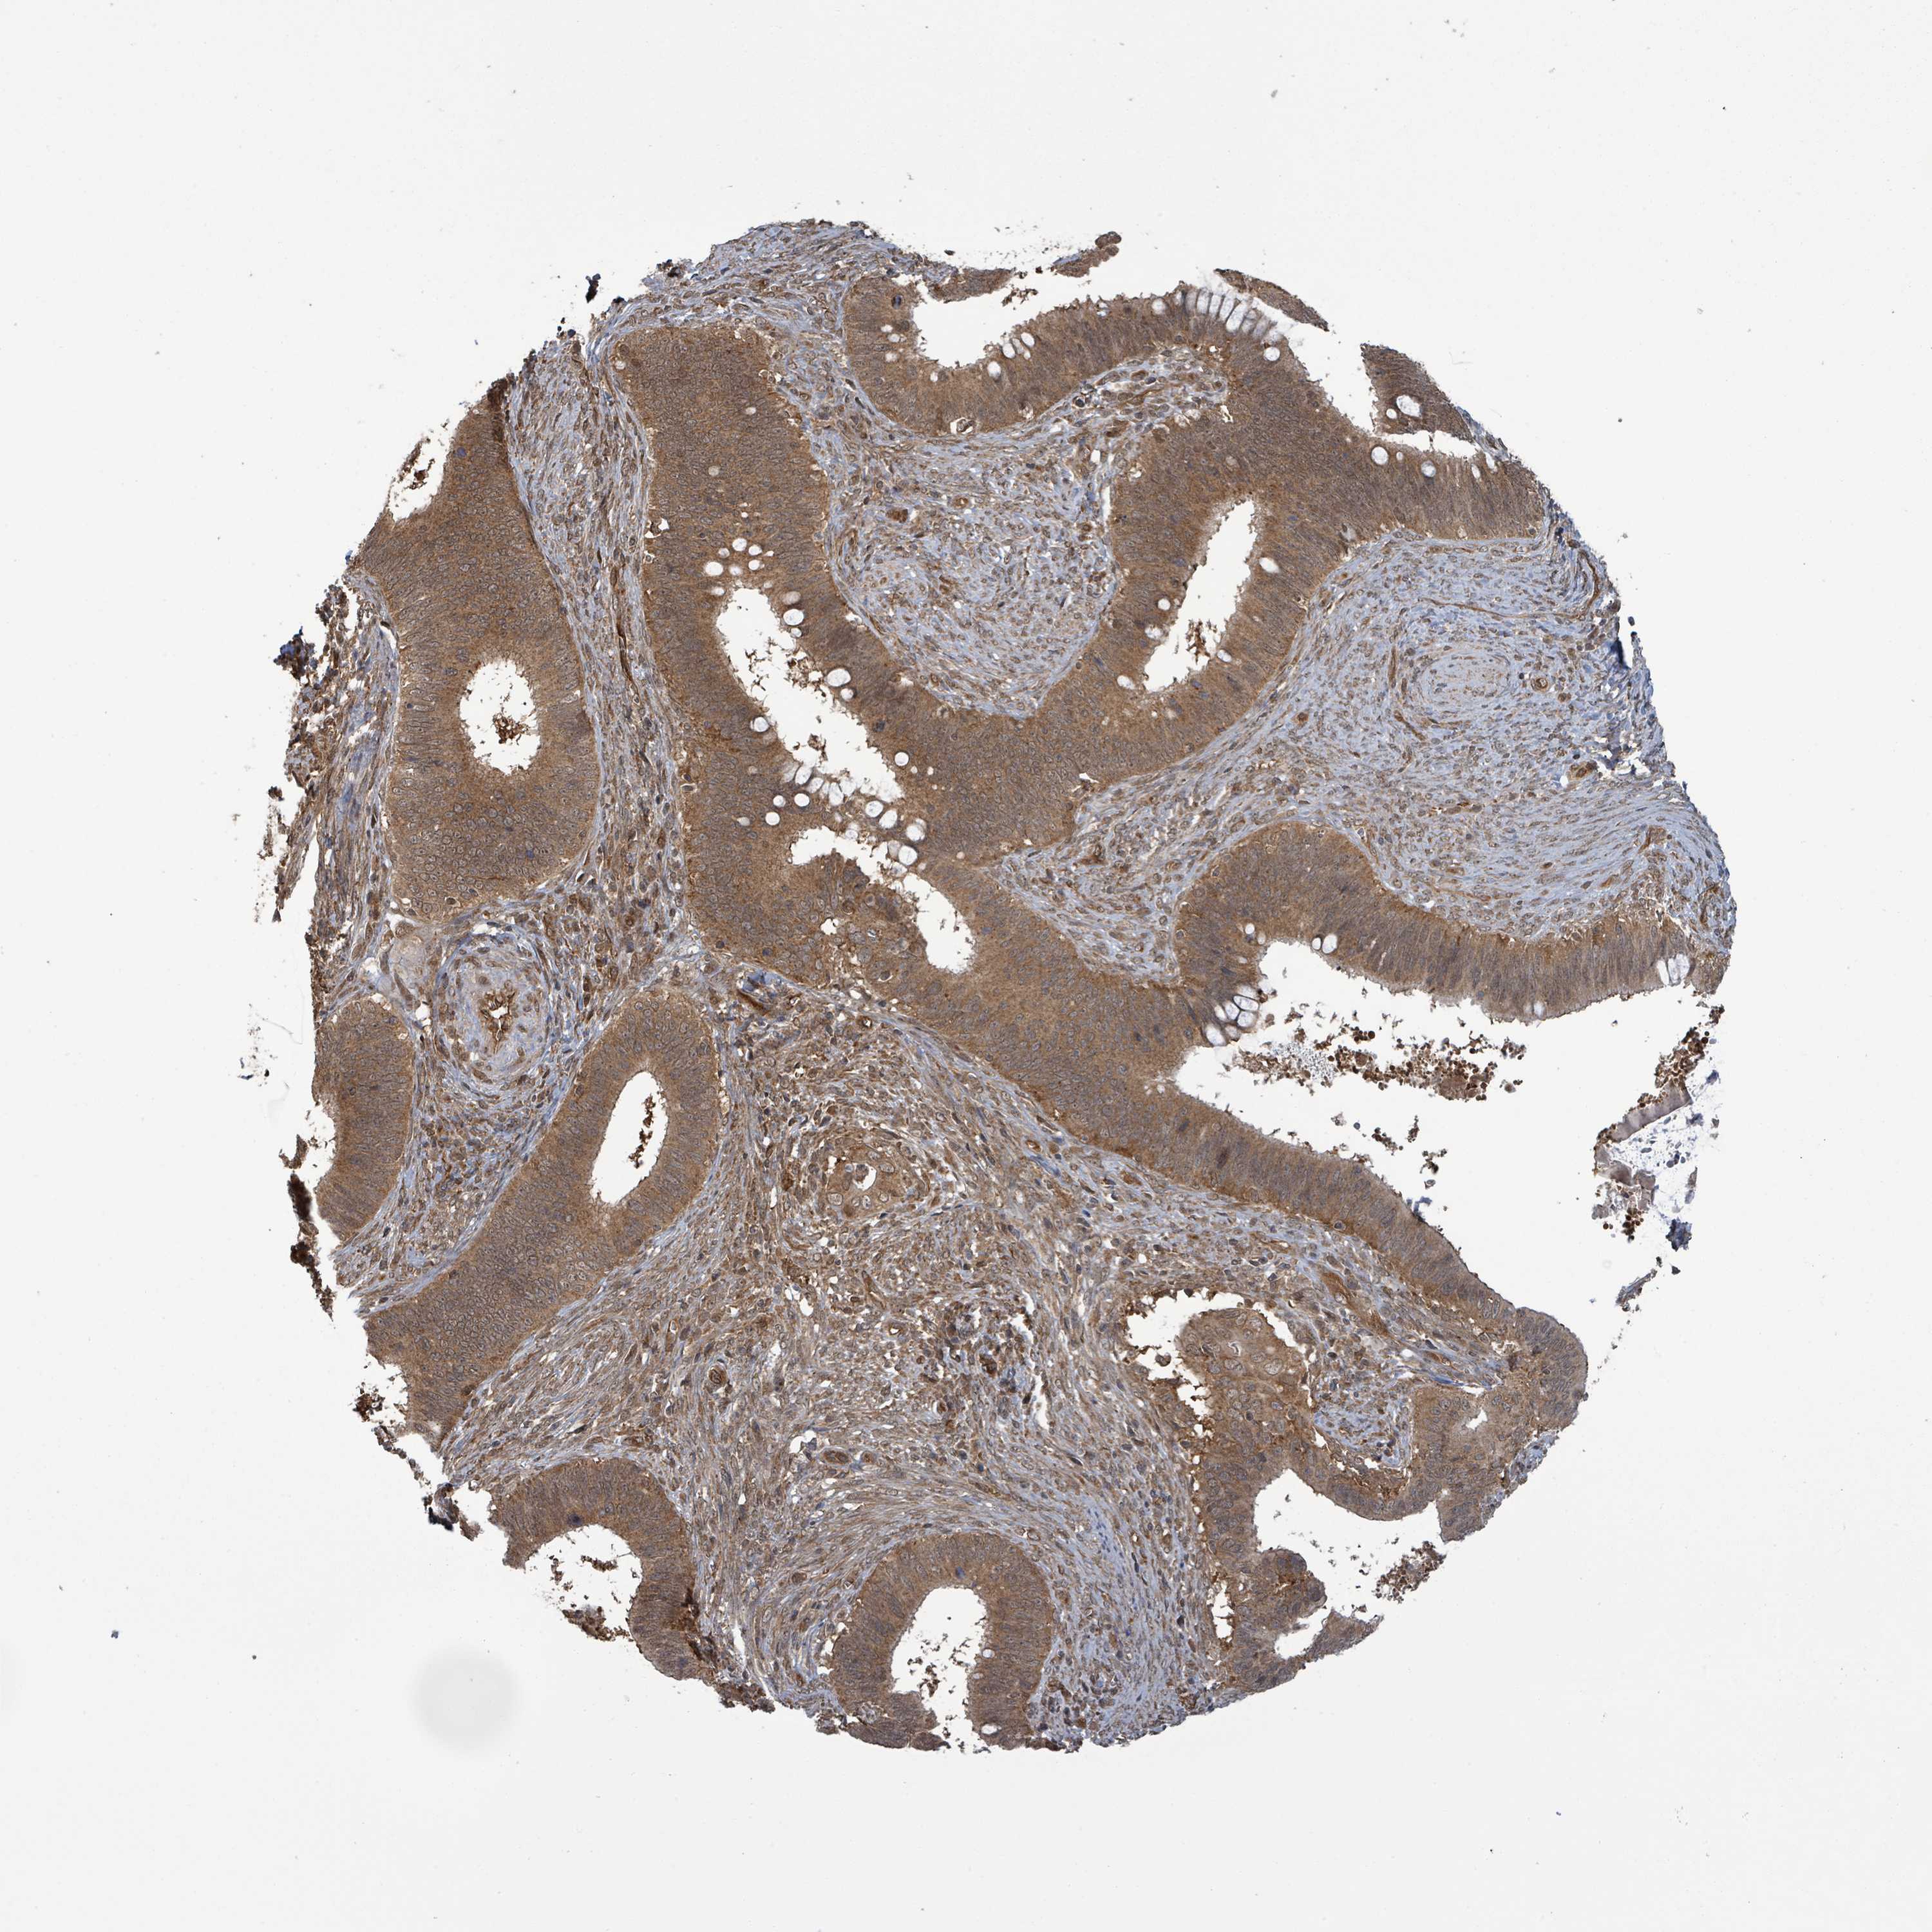

CERVICAL CANCER - Protein expressioni

A mouse-over function shows sample information and annotation data. Click on an image to view it in a full screen mode. Samples can be filtered based on level of antibody staining by selecting one or several of the following categories: high, medium, low and not detected. The assay and annotation is described here.

Note that samples used for immunohistochemistry by the Human Protein Atlas do not correspond to samples in the TCGA dataset.

Antibody stainingi

Antibody staining in the annotated cell types in the current human tissue is reported as not detected, low, medium, or high, based on conventional immunohistochemistry profiling in selected tissues. This score is based on the combination of the staining intensity and fraction of stained cells.

Each image is clickable and will lead to virtual microscopy that enables deeper exploration of all samples and also displays staining intensity scores, fraction scores and subcellular localization as well as patient and tissue information for each sample.

Antibody HPA044617

Squamous cell carcinoma, NOS